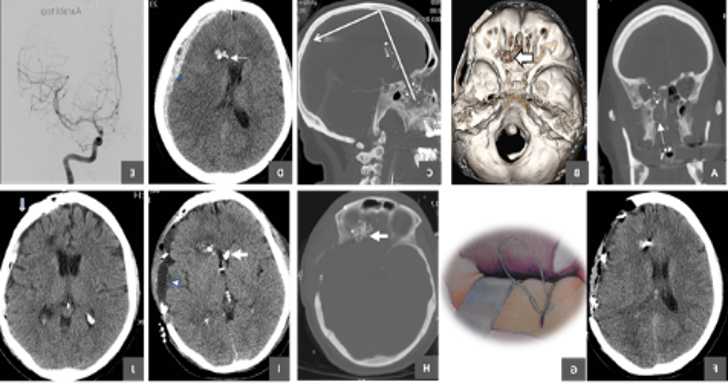

The multidisciplinary nature of these conditions extends beyond the surgical repair (Fig1). As the trajectory of the penetrating object often involves the superior sagittal sinus, anterior cerebral arteries, and potentially the basal cisterns, involvement of neurovascular and endovascular experts is often required as well. However, vascular injuries in pTBI are addressed in other aspects of these guidelines. Rehabilitation specialists are also required as well to achieve best outcomes. Rehabilitation not only helps to build muscle and adaptive strategies, it stimulates brain plasticity as well as other type of neural repair.

Self-inflicted gunshot wounds and blast injuries can frequently involve submental, intraoral and trans-temporal regions, causing injury to the face, orbits, air sinuses and frontal skull base. These injuries may occur in civilian or conflict environments and may be low velocity pTBI, gunshot wounds, or blast injuries.

Following review of the literature, no studies were found that compared a multidisciplinary with an isolated neurosurgical approach to pTBI of the face and orbits. As facial and orbital/eye repair is outside of the traditional training of most neurosurgeons, effective surgical treatment of these injuries is only possible through multidisciplinary teams. Although multiple individual operations are possible from each service, this approach carries the risk of multiple anesthetic administrations, increased risk of infection from additional operations, and potential disruption of previous surgical repair. For example, access to the orbit and forehead after cranialization of the frontal sinus could potentially de-vascularize the pericranial graft and threaten the CSF leak repair.

In modern medicine, multidisciplinary care is essential to achieving best outcomes. pTBI patients can be extremely complex requiring the expertise of multiple medical and surgical disciplines. Therefore, a multidisciplinary teamwork approach to surgical management of pTBI involving face, orbits and frontal skull base is recommended. If these teams are not available, transfer to an appropriate facility with these services after medical and surgical stabilization is also recommended. Even the neurosurgical care may require the involvement of multiple neurosurgeon subspecialists such as those with advanced trauma, vascular, skull base and spine training.